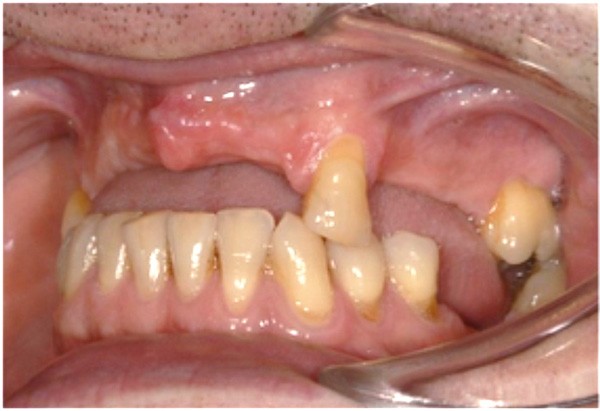

Cette partie de la présentation ne se contentait pas de rapporter les principes précédemment décrits à des régions limitées des maxillaires mais étendait la discussion à la difficulté majeure rencontrée en implantologie : rattraper des erreurs de positionnement implantaire ayant entraîné des compromis prothétiques inesthétiques. La solution thérapeutique mise en œuvre par Benoît Philippe consiste à appliquer la procédure d’ostéotomie segmentaire à l’entité constituée par l’os alvéolaire péri-implantaire et les implants. Les couronnes implantaires sont déposées. Le tracé d’ostéotomie encadre le segment à repositionner mais n’implique pas la corticale palatine qui sera fracturée pour éviter toute lésion du périoste (nourricier du segment alvéolo-implantaire). Un dispositif prothétique préparé en amont guide la translation du fragment qui est fixé au moyen de plaque d’ostéosynthèse dans la situation idéale. Le capital squelettique est reconstruit et l’espace prothétique disponible est normalisé.

Au cours de la conférence, Benoît Philippe a énoncé ses convictions concernant les conditions de succès du traitement implanto- prothétique : le respect d’une biomécanique implantaire équilibrée, le recours à des implants plus fins et moins nombreux que ne l’imposaient les préconisations d’autrefois, l’observation du biotype parodontal plus ou moins favorable aux reconstructions des atrophies étendues, la nécessité de restaurer au préalable puis de maintenir un environnement parodontal satisfaisant (en particulier la gencive attachée péri-implantaire).

La procédure chirurgicale du cas est à visionner sur : www.idweblogs.com